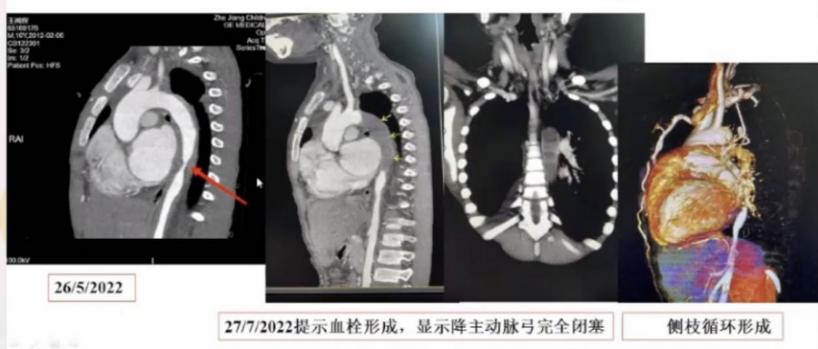

什么是加用治疗大动脉炎的诊断与治疗,看这篇就够了_https://www.jmylbn.com_新闻资讯_第1张图1:患者影像学资料

很快,患者出现了血栓形成,影像学显示降主动脉弓完全闭塞,侧枝循环形成。